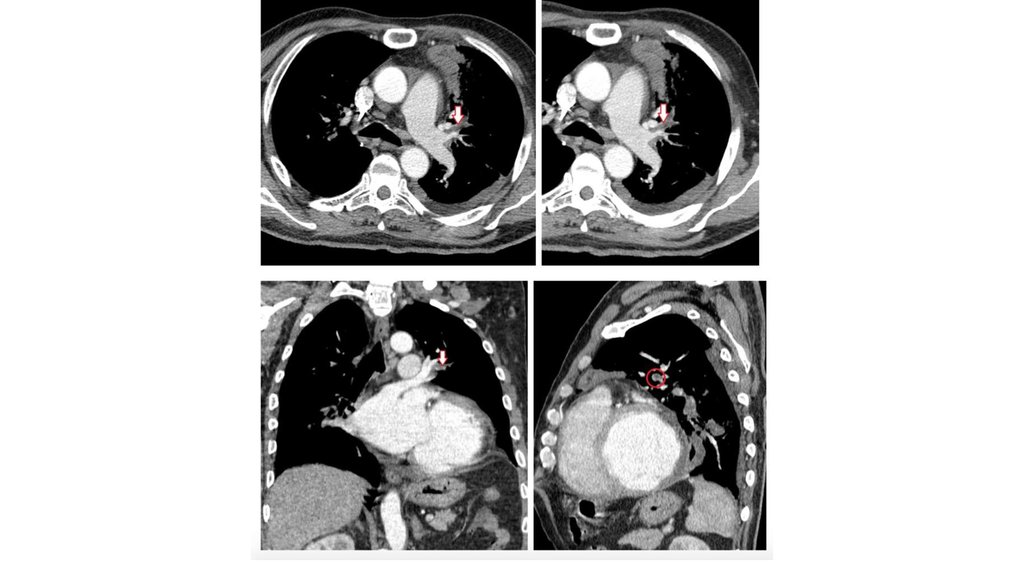

• КТ ангиография

Дисфункция ПЖ увеличения индекса конечно диастолического

диаметра ПЖ/ЛЖ

• Эмболия верхнедолевой легочной артерии слева,

выявленная при КТ органов грудной клетки с контрастом:

отчетливо визуализируется эмбол в просвете артерии

(отмечен стрелками и кружком)